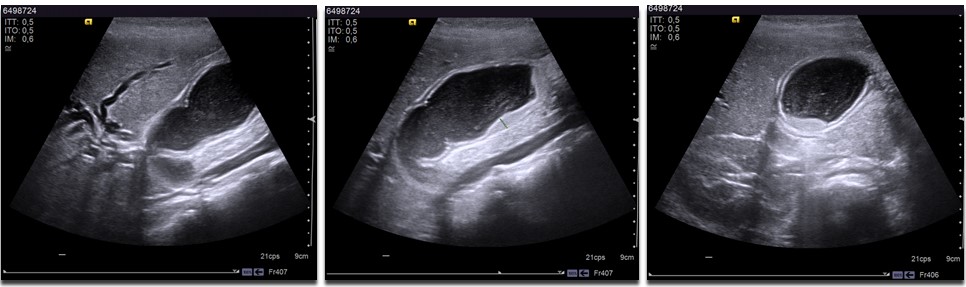

Niña de nueve años, sin antecedentes personales ni familiares de interés, que acude a su centro de salud porque desde hace tres semanas presenta astenia, hipocolia y coluria. En la última semana asocia ictericia y prurito. A la exploración física destaca ictericia intensa de piel y conjuntivas, así como hepatomegalia de 3 cm, a expensas de ambos lóbulos y de consistencia aumentada. En analítica sanguínea se objetiva elevación de marcadores de colestasis (AST 472 U/I, ALT 804 U/I, GGT 318 U/l, fosfatasa alcalina 772 U/I, bilirrubina total 7,1 mg/dl, bilirrubina directa 4,7 mg/dl y colesterol 290 mg/dl). Se amplía estudio para descartar etiología infecciosa, autoinmune y metabólica del cuadro, con resultados normales. En la ecografía abdominal (Fig. 1) se observa dilatación de vía biliar intra y extrahepática, así como vesícula biliar distendida y barro biliar en su interior. Ante los hallazgos descritos se decide ingreso, pautándose tratamiento con dieta hipograsa y ácido ursodesoxicólico. Ante empeoramiento analítico y ecográfico, pasadas 24 horas, se añade al tratamiento antibioterapia con cefotaxima con la sospecha de colangitis asociada, con buena evolución clínica, analítica y ecográfica posterior. Previo al alta, se realiza una colangiorresonancia magnética en la que se objetiva un brusco cambio de calibre en la porción intrapancreática del colédoco sin causa extrínseca que lo justifique, y que en el contexto clínico sugiere una estenosis congénita a ese nivel. Con estos hallazgos se programa una colangiopancreatografía retrógrada endoscópica, en la que se realiza esfinterotomía y dilatación con balón con colocación de dos prótesis. Dos meses más tarde presentó nuevo episodio de colangitis leve que se controló con ciclo antibiótico. Buena evolución posterior, pudiéndose retirar las prótesis un año tras el procedimiento y permaneciendo asintomática hasta la actualidad.

Figura 1. Ecografía con hallazgos de vesícula biliar distendida y barro en su interior.